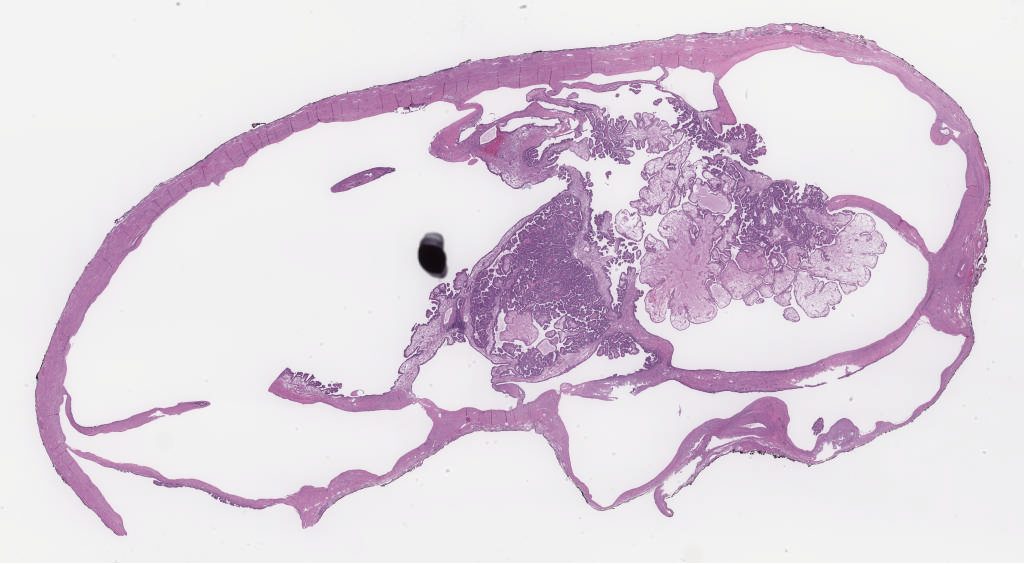

1066175.svs

87647

48234

40X